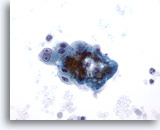

画像 3

肝FNA – 良性肝細胞

核はわずかに大小不同であり、反応性変化を来した肝細胞に典型的な低N/C比を示します。微小な細胞質空胞および細胞質内色素がみられます。

60倍

画像 3

肝FNA – 良性肝細胞

核はわずかに大小不同であり、反応性変化を来した肝細胞に典型的な低N/C比を示します。微小な細胞質空胞および細胞質内色素がみられます。

60倍